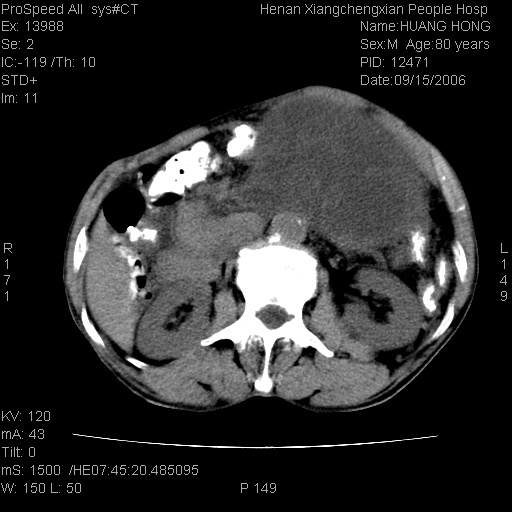

患者, 男, 80岁, 发现上腹部包块1年余,无其它不适.2006-9-14ct片是喝水后扫描2006-9-15ct片没喝水扫描![]() ![]() ![]() ![]() ![]() ![]() ![]() ![]() ![]() ![]() ![]() ![]() ![]() ![]() ![]() ![]() 以上是喝水片 以下是空腹片 ![]() ![]() ![]() ![]() ![]() ![]() ![]() ![]() ![]() ![]() ![]() ![]() ct:胰腺前方、肝脏与胃之间可见巨大类圆形囊性低密度影,大小约152mmx145mmx118mm,上缘平t11椎体上缘,下缘平l3椎体下缘,密度均匀,ct值15hu,其内呈多房分隔,囊壁薄且光滑,边界清晰,周围组织及器官明显受压。肝脏实质内未见异常密度影,胆囊未见异常,胰腺密度未见异常,脾脏大小、形态及密度未见异常,腹膜后间隙未见肿大淋巴结影。 印象:胰腺前方、肝脏与胃之间巨大类圆形囊性低密度影.性质待定。多考虑:.肠系膜巨大囊肿。 守望可可西里发言:支持楼主,考虑肠系膜囊肿,多为小肠系膜。 ysxyy发言:我总觉得这个病人虽然很像肠系膜囊肿,但还是应该强化一下; 下面这几幅图里肿块和主动脉的关系不太清,不知能否除外血管性来源? ![]() ![]() ![]() 病理结果:横结肠系膜间叶瘤.部分区域间质细胞增生活跃. 病理图片 ![]() 良性间叶瘤:是指由两种或两种以上的间叶组织所构成的混合性肿瘤.肿瘤仅发生在腹膜后和肠系膜,.前者较后者多发.良性间叶瘤常发生在肾或四肢,腹膜后较少见,各年龄均可发病.女多与男,预后较好,但术后易复法. 恶性间叶瘤:由两种以上恶性间叶组织成分组成. 光镜:肿瘤由脂肪/血管/平滑肌构成. 原贴地址: http://www.radinet.com.cn/forum_view.asp?forum_id=4&view_id=16217 ok |